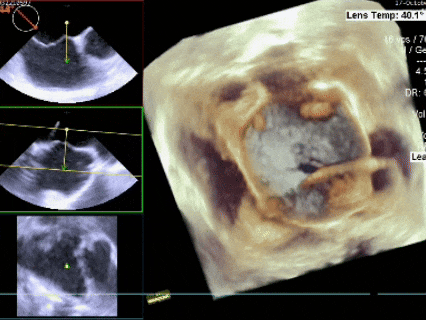

锁定后评估

彩色多普勒血流成像显示无残余分流存在

释放后评估

释放后多切面下观察

封堵器位置正确、形态良好